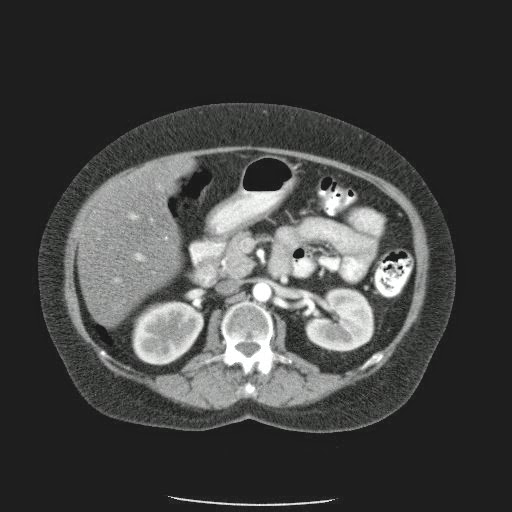

Caso Interesante #4

Adulto masculino, 1 semana de fiebre y malestar general.

¿Dónde esta ubicado el hallazgo?